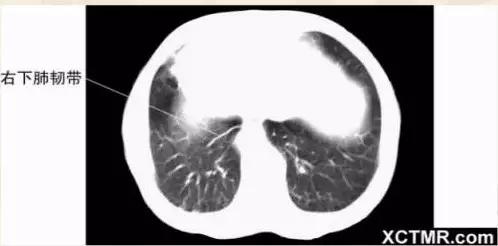

肺段划分